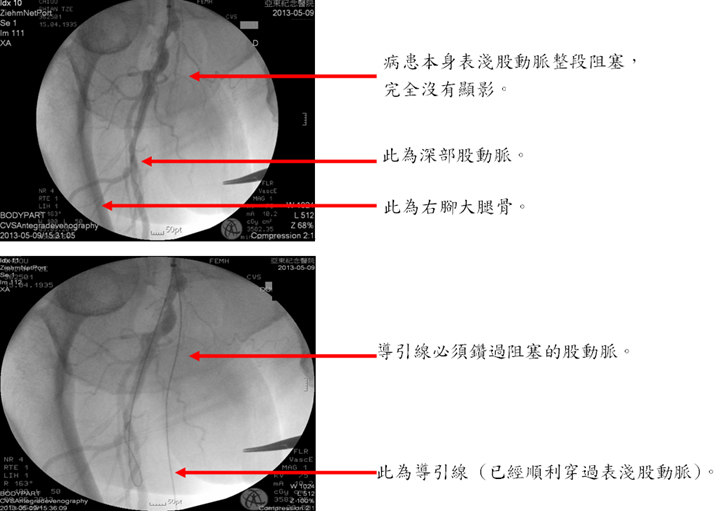

本院心臟血管外科在引進先進的手術室血管攝影設備之後,便極力整合血管內治療與外科手術兩方面。 一個病人,在同樣一次的麻醉程序中,在超音波導引之下,在血管內放入導管。先以血管攝影確認診斷與必須處理的部位,然後對於適合血管內治療的部位施以氣球擴張或支架置放術, 對於適合手術治療的部位,則施以繞道手術。如此一來,患者的下肢動脈阻塞疾病可以在最短的時間內一次解決,肢體保留的機會自然增加,省去了常令患者極度沮喪的截肢。